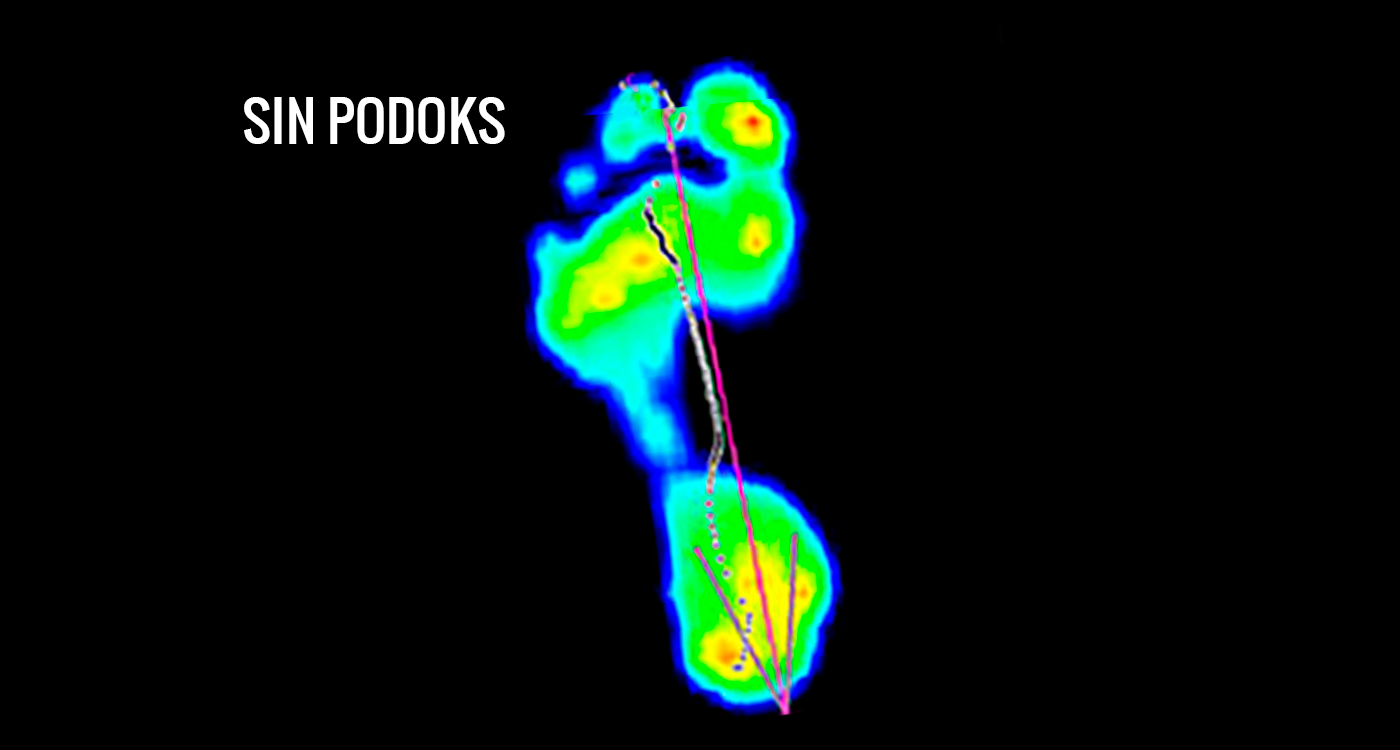

ANTES / DESPUÉS

Observa los beneficios de utilizar un calcetín con la tecnología de podoks.

(DESLIZA Y COMPRUÉBALO TÚ MISMO)

Sin Podoks – Presiones plantares en pie izquierdo, llevando su propio calcetín, en paciente con hiperpresión en la primera cabeza metatarsal asociada con hiperqueratosis leve bajo la misma.